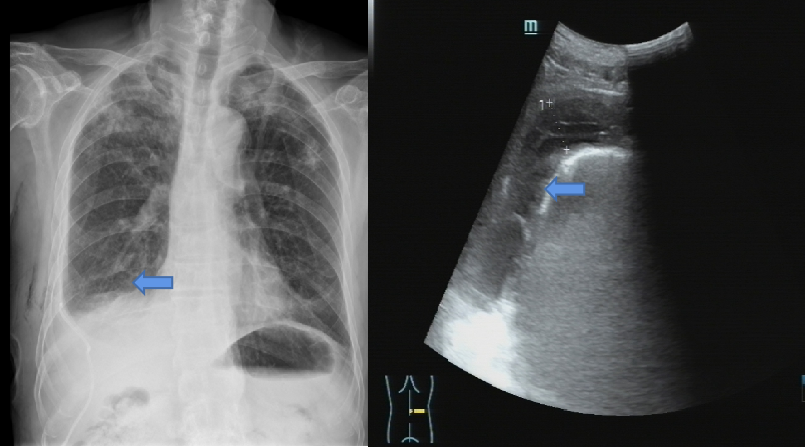

罗少华主任带领呼吸内镜介入团队,为患者行经胸腔镜下胸膜活检术+胸膜黏连烙断术(见图3-5),过程顺利,呼吸困难明显减轻,术后予以胸腔闭式引流术+胸腔内纤溶性药物注射,复查胸片及胸腔积液超声,包裹性胸腔积液情况明显减轻(见图6)。

图7:术后胸片及胸腔积液超声提示包裹性积液明显减少(蓝色箭头区域未见明显包裹)